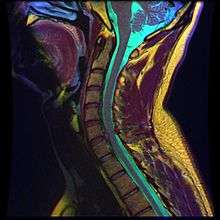

A spinal disc herniation demonstrated via MRI. | |

- Magnetic resonance imaging (MRI): A diagnostic test that produces three-dimensional images of body structures using powerful magnets and computer technology. It can show the spinal cord, nerve roots, and surrounding areas, as well as enlargement, degeneration, and tumors. It shows soft tissues even better than CAT scans. An MRI performed with a high magnetic field strength usually provides the most conclusive evidence for diagnosis of a disc herniation. T2-weighted images allow for clear visualization of protruded disc material in the spinal canal.